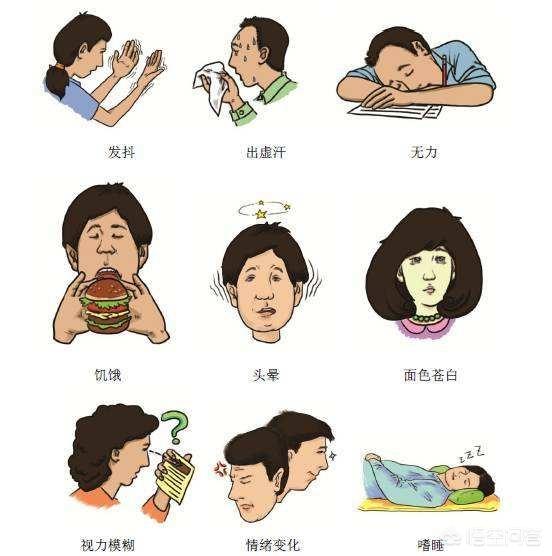

まず、低血糖症状の兆候とは何かから説明しよう。

1.一般的に自律神経機能が過剰に興奮した状態になり、パニック、手の震え、発汗、異常感覚、空腹感などの症状が現れ、夜間発作であれば突然の覚醒につながる。

2.めまい、倦怠感、無反応、精神異常、意識消失などの脳機能障害の症状も現れることがある。

低血糖の基準は終末血糖値が3.9mmol/L以下である。 アドバイス:低血糖の一般的な症状には、偽発汗、手の震え、空腹感、ふるえ、いらいら、顔面蒼白などがあります。